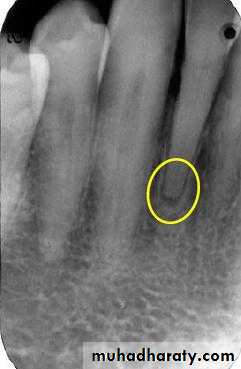

Radiographic Features:

Most lesions are discovered on routine radiographic examination.A well-defined radiolucency of bone apical to the offending tooth. Loss of the apical lamina dura.

The lesion may be circumscribed or ill defined.

The size is variable.